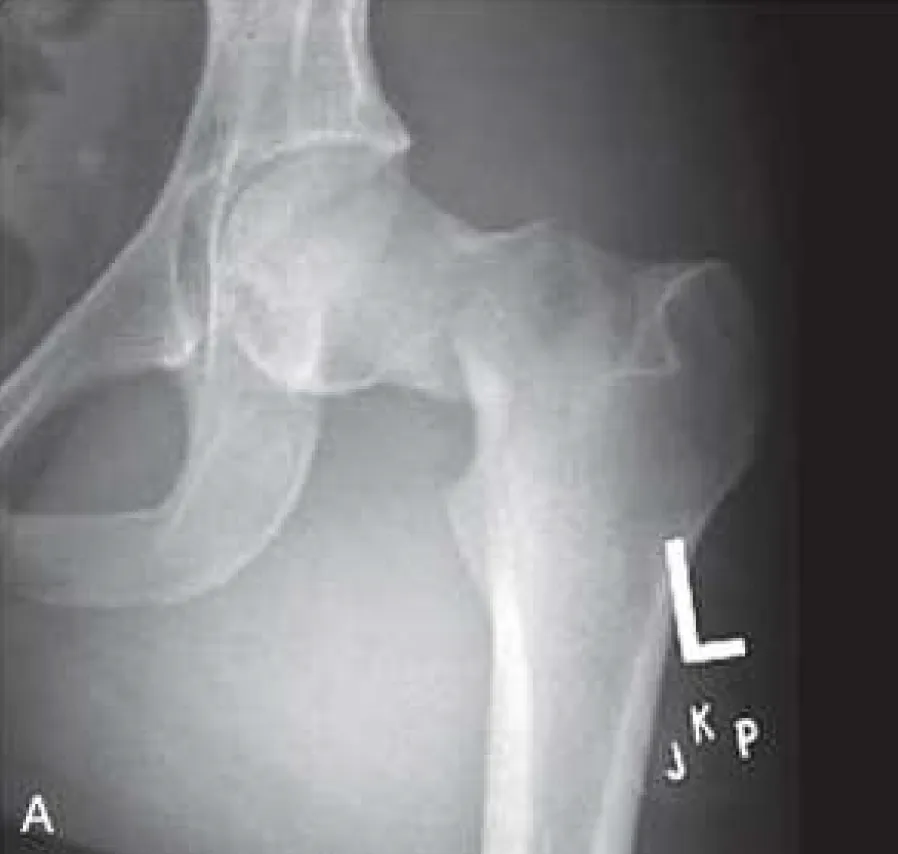

這題的解題核心在於仔細觀察股骨頸骨折的X光片,並辨識出股骨頭與股骨幹之間的相對位置變化,特別是Shenton's line的連續性。